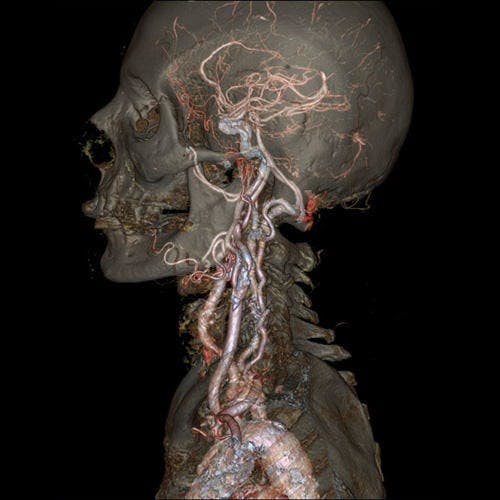

自從X光發明之後,X光電腦斷層掃描一直以來在醫學上都是重要的應用,尤其是檢查腦血管、心血管以及腫瘤篩檢等方面。不過在影像清晰方面仍然有些麻煩,只要患者有一些小小的震動,影像就會模糊。不過若是使用這次GE所發表的革命性電腦斷層掃描,醫生能夠拍下一個完整影像清晰的心臟。

自從X光發明之後,X光電腦斷層掃描一直以來在醫學上都是重要的應用,尤其是檢查腦血管、心血管以及腫瘤篩檢等方面。不過在影像清晰方面仍然有些麻煩,只要患者有一些小小的震動,影像就會模糊。不過若是使用這次GE所發表的革命性電腦斷層掃描,醫生能夠拍下一個完整影像清晰的心臟。